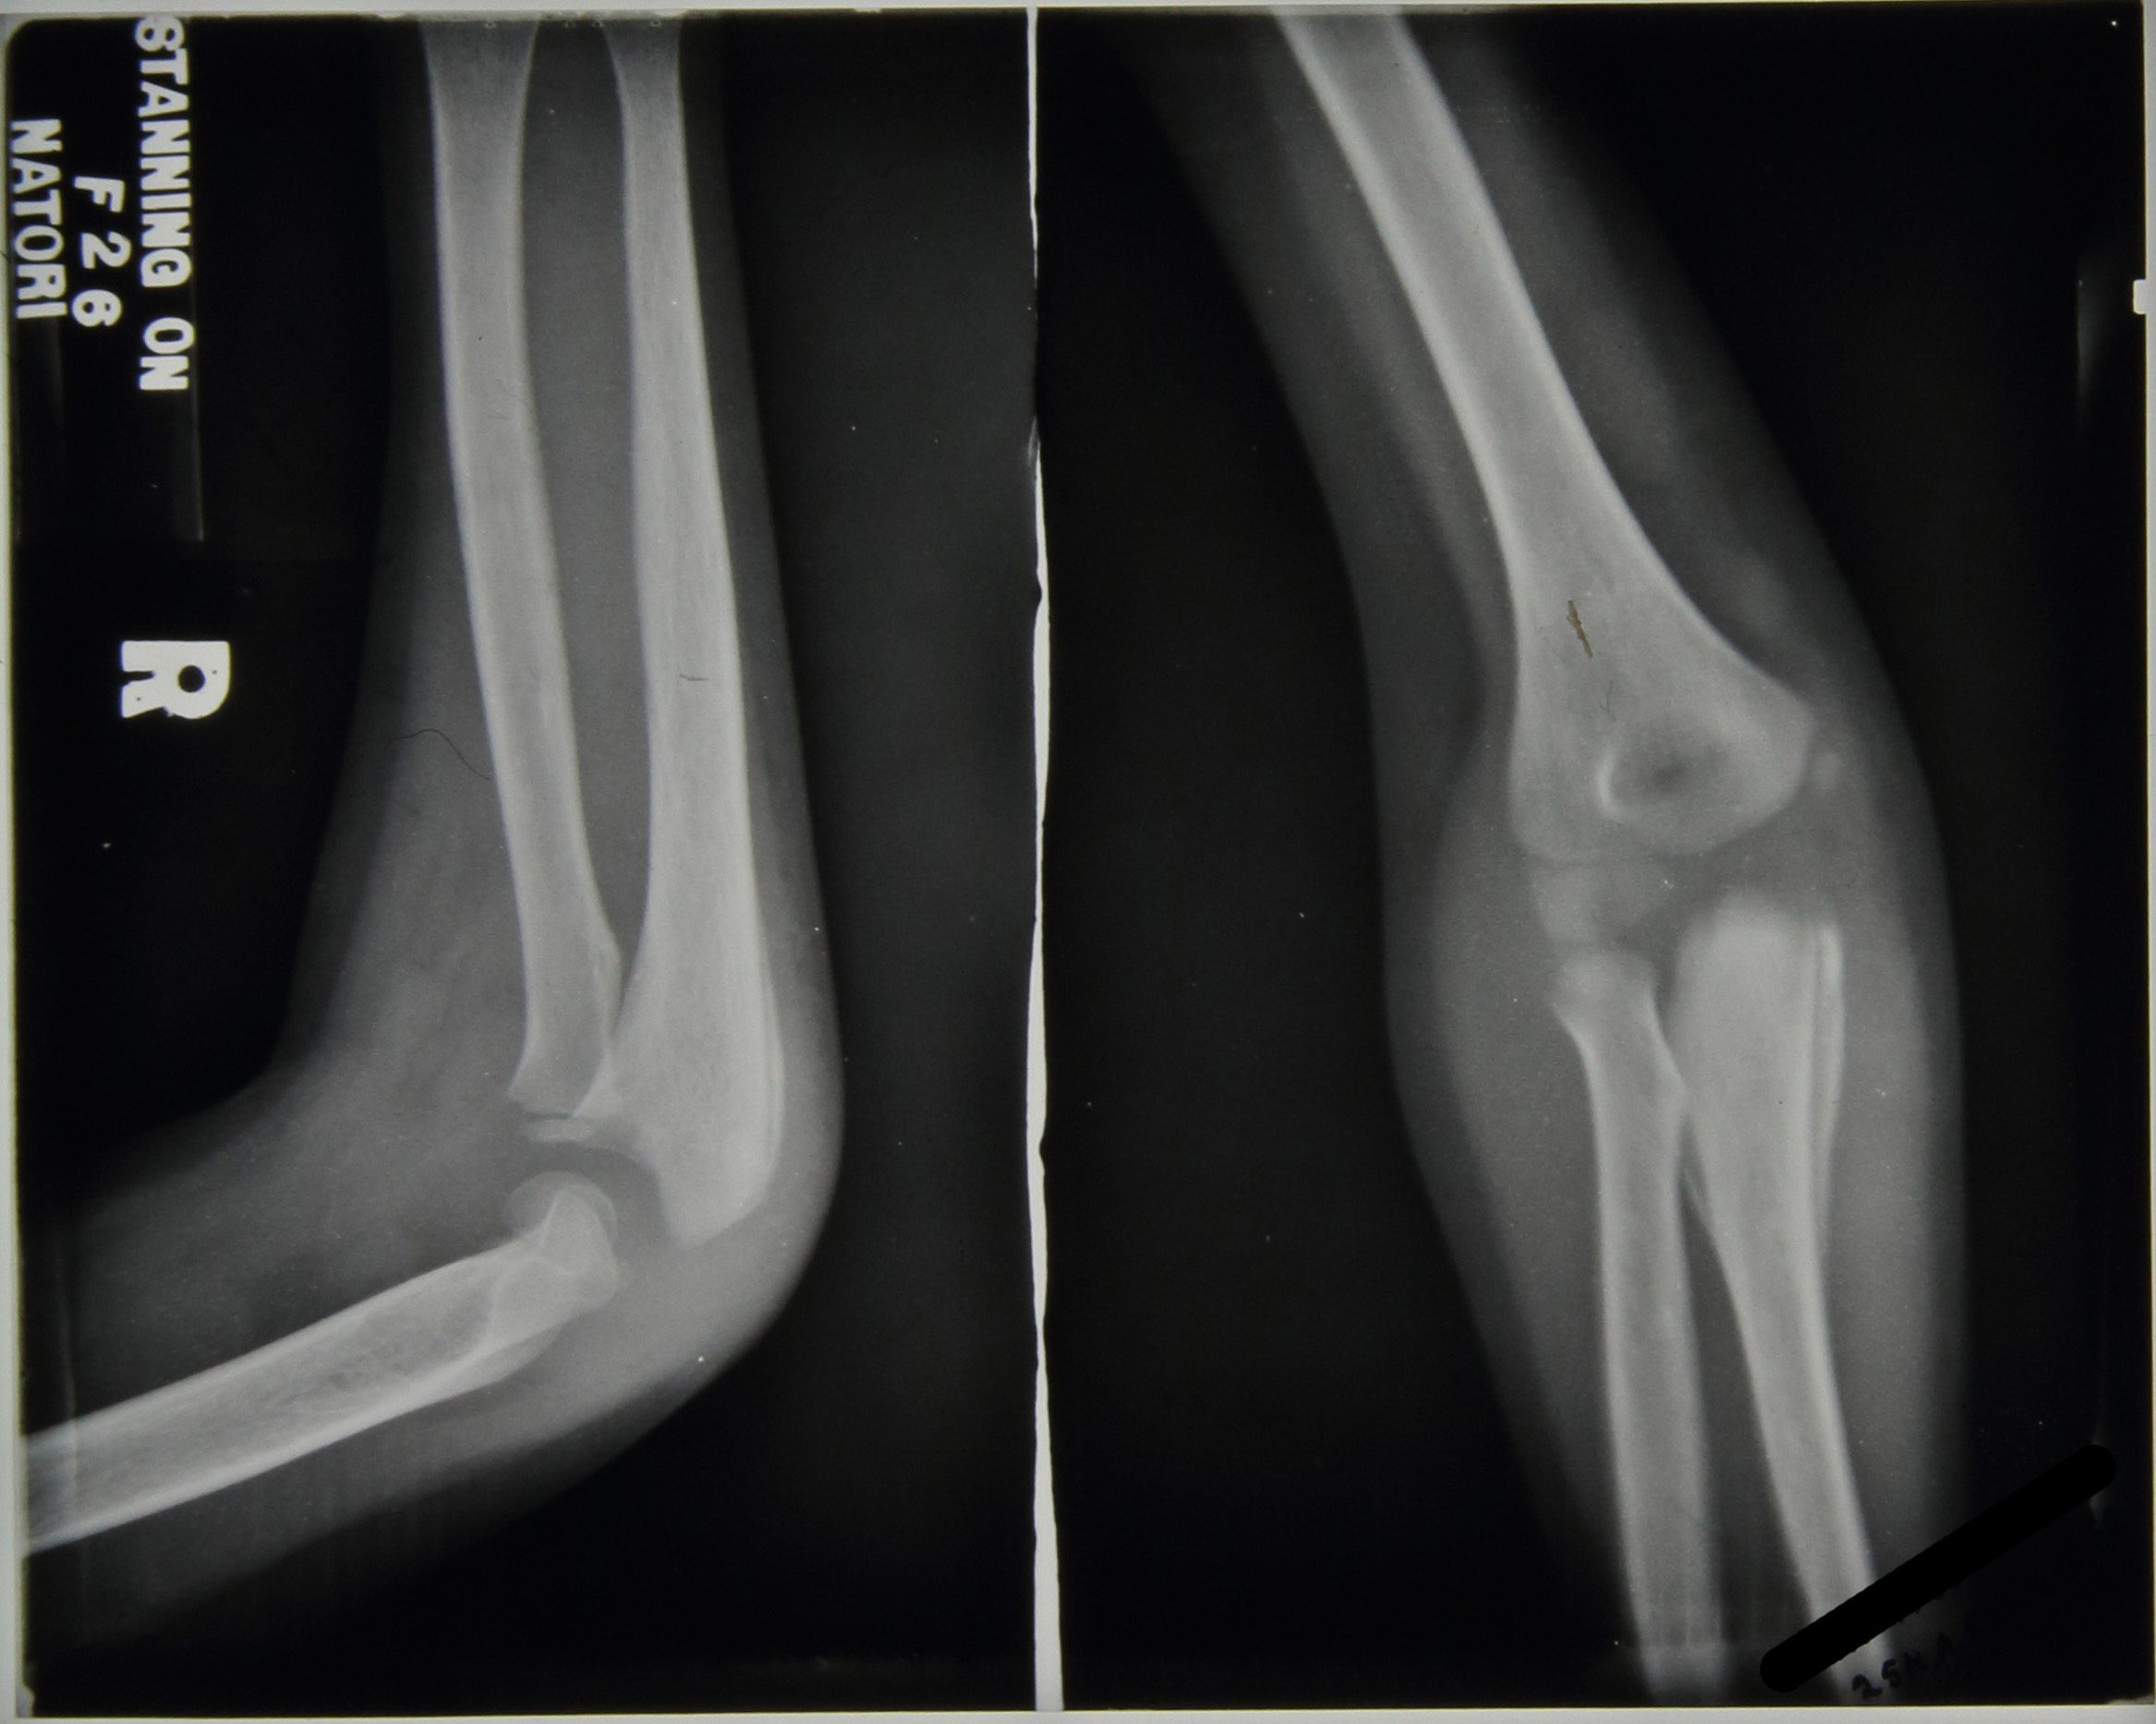

The main focus of the notes centre upon the right elbow which, in September 1938, was described as being very active with discharging abscesses; periostitis was greatly increased in the ulna and also present in the humerus with the joint being ‘badly involved’, see Figure 4. In November 1938 large sequestrum was removed from the elbow, at this time all lesions were considered very active. The elbow continued to be active with an increasing number of ulcers noted to have appeared; a maximum of four seen in February 1939 including one in the right cubital fossa which is incised to produce ‘copious…pus’, Figure 5.

X-ray reports from September 1939 read as follows:

11/9/39 – Ulna hollowed out to cavity

Radius dislocated upward & forward

Lower end humerus eroded & partly destroyed.

15/9/39 – Ulna – upper end partially destroyed, disorganisation of elbow joint’

No further comment is made regarding a diagnosis of tuberculosis in the elbow.